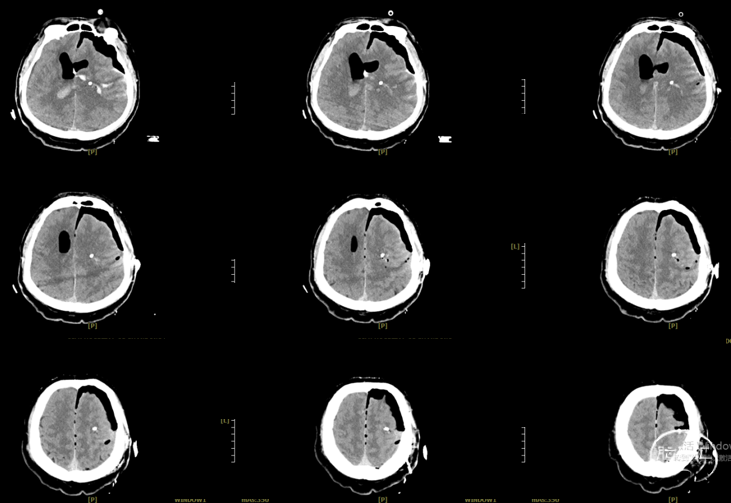

气管插管全麻成功后,患者取平卧位,上半身抬高20°,头微屈,头架固定,延导航标记左侧冠状缝前3cm,中线旁开3cm弧形手术刀口,长度约5cm,常规消毒铺巾,依次切开皮肤、皮下及骨膜各层,钻骨孔一个,铣成大小约3.0cm*3.0cm骨窗,电灼硬膜,“十”字状切开硬膜,置神经内镜,探查左侧基底节发现大量暗红色脑内血肿,内镜下彻底清除基底节区血凝块约80ml后脑组织压力较前明显降低,见血肿前方、侧方深部各有活动性出血,血肿底部可疑小型异常血管团,予以电凝彻底止血,并切除部分送病理,止血材料覆盖血肿腔,术区冲洗未见活动性出血,向内侧沿着血肿破入脑室痕迹探查,暴露脑室体部,清除脑室内大量血凝块,并反复使用生理盐水冲洗,再次探查见基底节区血肿腔止血充分,无活动性出血,温盐水冲洗术野,使用流体明胶压迫并接触止血,血肿腔留置12号侧脑室引流管1根,硬膜下留置codman颅内压传感器一根(偏移值520),以连接板将骨瓣还纳,清点棉片器械无误,依次缝合皮下及皮肤各层。将引流管皮下潜行后固定引流管,手术顺利,术中出血约20ml,未输血,术后呼吸改善,复查CT示基底节及脑室内血肿清除满意,带气管插管安返我科监护室。

2026.3.15:

2026.3.26: